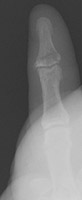

- Click on the image for a larger versionEOblique radiograph of the first digit. This shows a fracture of the distal phalanx.

- Click on the image for a larger versionFPA radiograph of the first digit. This also shows the distal phalanx fracture.